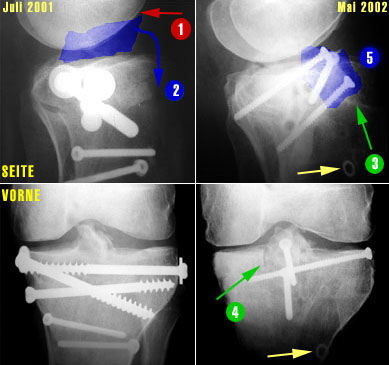

Und so sieht das ganze radiologisch aus (links die Bilder vom Juli 2001 mit den 5 alten Schrauben, rechts die Bilder vom Mai 2002 mit den 3 neuen Schrauben - auf die Bildfragmente klicken, um eine grössere Fassung des Ausschnittes zu sehen).

1. Das Problem, Bild links oben: Die zu hoch eingewachsene Eminenz (im Kniegelenk höchster Teil des Schienbeins, blau eingefärbt) verhindert die Streckung, weil sie am Oberschenkel anstösst, wenn das Bein gestreckt werden sollte (1).

2. Die Lösung: Weil an der Eminenz Bänder angewachsen sind, kann man das zu hoch stehende Fragment nicht einfach abhobeln - man muss es nach unten ziehen (2). Dafür muss aber zuerst Platz geschaffen werden...

3. Die Ausführung: Am Schienbein werden diverse Schnitte vollzogen. Im Bild rechts oben (3) ist der Schnitt von vorne sichtbar, im rechten unteren Bild (4) ein Schnitt von oben. Aus dem Schienbein ein Keil entfernt, sodass die zuerst von überschüssigen Knochenfragmenten befreite Eminenz gewissermassen nach vorne und unten ins Schienbein geklappt werden und mit drei Schrauben festgemacht (5) werden kann. In den unteren beiden Bildern ist auch schön sichtbar, dass die Eminenz nun wieder eine normalere Form hat.

Schön sichtbar sind auch die alten Löcher der im November 2001 entfernten Schrauben sowie in den Bildern rechts (gelbe Pfeile) eine alte Unterlagsscheibe, die während dem Sommer 2001 im Knochen festgewachsen war und im November nicht herausgefischt werden konnte (auf die Bildfragmente klicken, um eine grössere Fassung des Ausschnittes zu sehen).